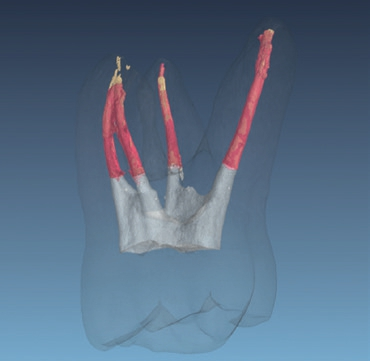

Bild: Prof. Dr. S. Grandini, Universität Siena, Italien.

Bild: Dr. F. Paqué, Universität Zürich, Schweiz.